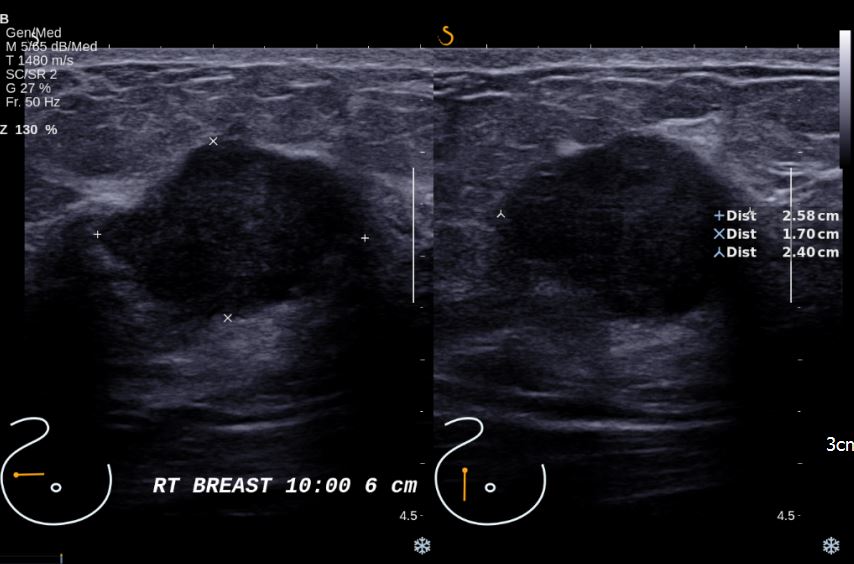

한달전에 우측유방 멍울 발견하여 정밀검사위해 내원하신 50대 여자분으로 초음파진행후

우측유방 10시방향으로 의심스런 혹이있어 중심핵생검 실시한후 침윤성 유관암 진단되셨습니다